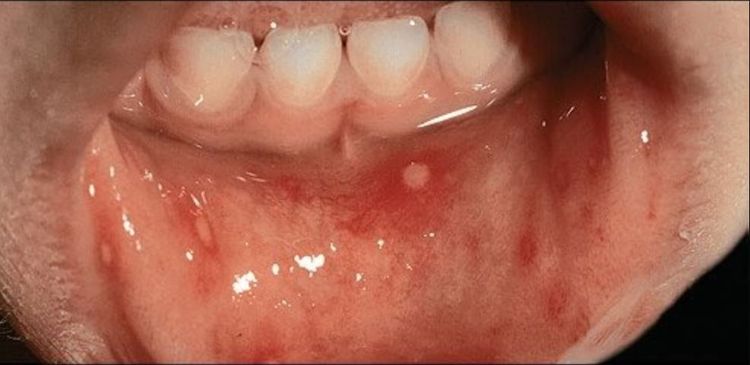

Bệnh tay chân miệng là một bệnh truyền nhiễm phổ biến nhưng khá lành tính, thường gặp ở trẻ nhỏ vào cuối mùa hè và đầu mùa thu. Coxsackievirus A16 và các chủng khác cùng loại là nguyên nhân gây ra bệnh. Các triệu chứng ban đầu bao gồm sốt nhẹ và khó chịu. Sau đó, trên vòm miệng, lưỡi, niêm mạc miệng và lưỡi gà của bệnh nhi sẽ xuất hiện các tổn thương dạng mụn nước, gây đau đớn và khó khăn trong việc ăn uống. Ở trẻ em nhỏ, tình trạng khó nuốt và chảy nước dãi do mụn nước ở miệng có thể dẫn đến mất nước, rất đáng lo ngại. Khoảng 1 – 2 ngày tiếp theo, các tổn thương này sẽ bắt đầu phát triển ở những bộ phận khác của cơ thể. Mụn nước có hình tròn hoặc bầu dục, bao quanh là một vầng hồng ban. Các cạnh của lòng bàn tay và lòng bàn chân là vị trí ưa thích của mụn nước, nhưng tổn thương vẫn có thể xảy ra trên toàn bộ cơ thể.

Nhiều tổn thương mụn nước nhỏ và rời rạc ở ngón tay, lòng bàn tay; tổn thương tương tự cũng xuất hiện trên bàn chân. Một số mụn nước thường dễ nhận thấy đường giới hạn xung quanh rõ ràng.